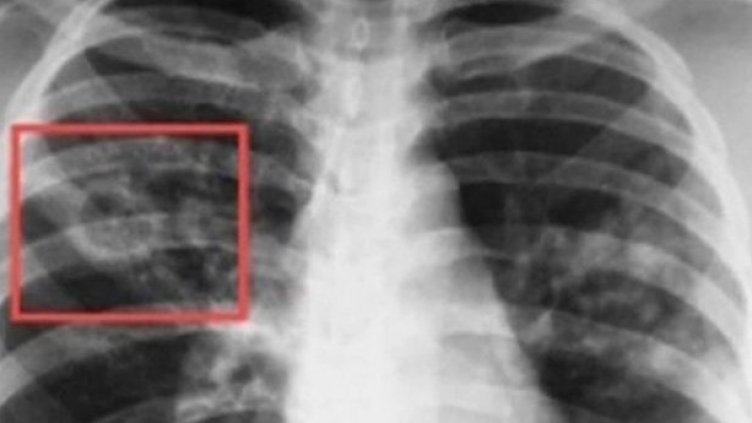

Целите на инициативата са да разшири възможностите за достъп до здравни услуги и да повиши обществената информираност по отношение на туберкулозата за симптомите, начина на заразяване, рисковите фактори, различните форми на заболяването, лечение и превенция.

По време на „Седмицата на отворени врати“ всеки желаещ може да се възползва от скрининг за риска от туберкулоза чрез анкета и консултация с лекар. На съмнителните за заболяване лица се извършват прегледи и допълнителни медицински изследвания.

При откриването на случаи на туберкулоза своевременно ще бъдат предприемани необходимите мерки за хоспитализация и лечение, в резултат на което ще се прекъсне веригата за предаване на инфекцията. Ранното откриване на туберкулозата и започване на своевременно лечение в дългосрочен план води до намаляване на случаите.

Въпреки значителните успехи, постигнати в борбата със заболяването в Европейския регион на СЗО и постоянния спад на случаите, туберкулозата продължава да представлява заплаха за общественото здраве в повечето страни от региона.

Благодарение на съвместните усилия на Министерството на здравеопазването, лечебни заведения за диагностика и лечение на туберкулозата и неправителствените организации, работещи с уязвимите групи за изпълнението на дейностите по Националната програма за превенция и контрол на туберкулозата, в страната се наблюдава тенденция за намаляване на заболяемостта от 23,8 на 100 хил. население през 2013 г. до 13,5 на 100 хил. през 2023 г.

Заболяването е лечимо и предотвратимо, стига да бъде открито навреме, да бъде проведено качествено лечение, съобразено с международните стандарти, като важно условие е пациентите да се придържат стриктно към лечението.

В България диагностиката, лечението и профилактиката на туберкулозата са безплатни за всички, които се нуждаят, независимо от техния здравноосигурителен статус.